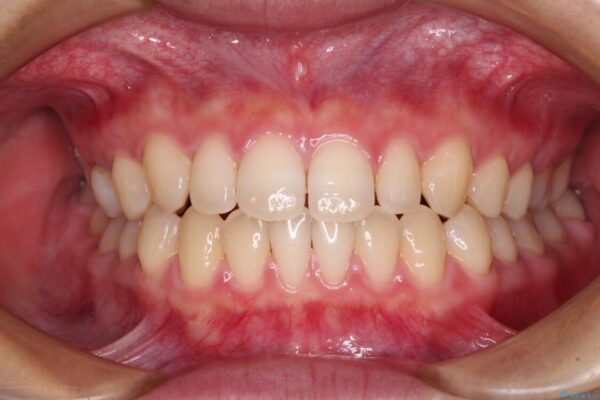

治療後

• 隙間だらけの歯列 インビザラインで改善 治療後画像